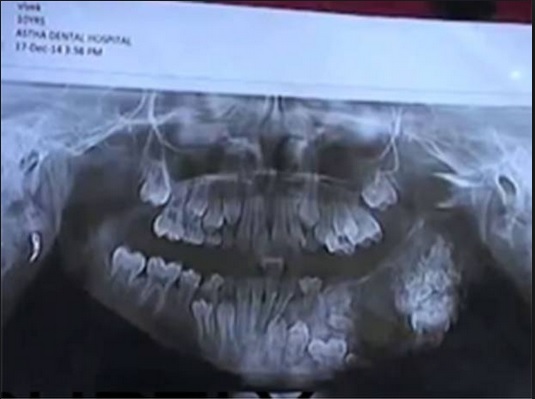

Tiến sĩ Maheshwari nói với tờ The Times of India rằng: “Bệnh nhân đã được chuyển tới viện 5 ngày trước khi bị tụ mủ ở hàm trên. Sau khi tiến hành kiểm tra, cậu bé được trẩn đoán bị u răng. Chúng tôi đã lên kế hoạch phẫu thuật và loại bỏ 80 chiếc răng sau khi hút hết mủ từ chỗ áp xe rất hiếm thấy ở độ tuổi này”.

U răng là loại khối u hiếm ảnh hưởng tới hàm hoặc nướu (lợi), tập trung cấu trúc vào cấu trúc răng.

Báo chí địa phương cho biết cậu bé tên Vivek. Bệnh nhân dường như đã phát triển một khối u ở bên trái miệng và được đưa tới viện MY sau khi điều trị tại làng thất bại.